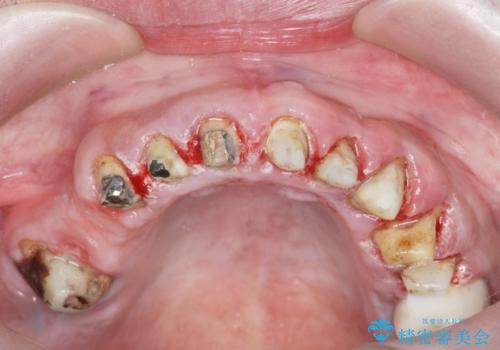

- 前医で行った前歯セラミック形態の改善、常に腫れぼったく歯ブラシの際に出血のある前歯部の治療を希望され来院されました。

前医により、前歯は歯ぐきの奥深くまで形成されこのままの状態でセラミックをやりかえたとしても歯ぐきの腫れの改善は難しい状況です。

歯周外科を行い歯と歯槽骨・歯肉の関係を是正することで歯ぐきの状態を改善し、将来に亘り安定した歯周環境の維持を期待できるセラミック治療を実践します。